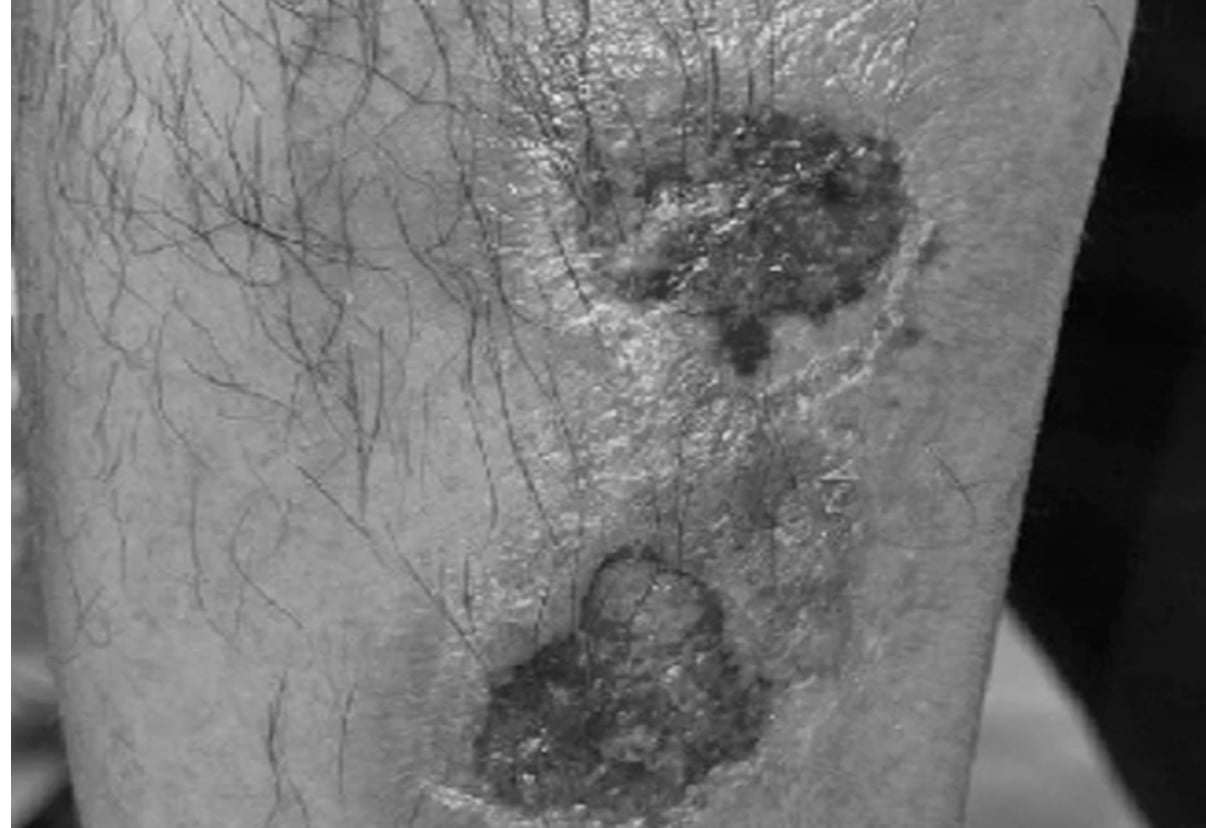

Trường hợp bệnh nhân nam, hơn 50 tuổi, mắc bệnh lichen phẳng (một trong những bệnh thuộc nhóm bệnh da có sẩn và bong vảy), tự ý uống thuốc với liều 10 mg/ngày trong 5 ngày liên tục thay vì 10 mg/tuần theo hướng dẫn trong đơn thuốc. Sau 5 ngày sử dụng thuốc, các tổn thương rát đỏ, phù nề, đau rát vùng sinh dục – hậu môn xuất hiện, nhưng bệnh nhân vẫn tự ý mua thêm uống tiếp trong 5 ngày với liều tương tự. Khi tổn thương tiến triển nặng hơn, bệnh nhân phải đến Bệnh viện Da liễu trung ương để điều trị.

Vết tổn thương của bệnh nhân do sử dụng thuốc sai cách.

Bs CKII. Đặng Bích Diệp, Khoa điều trị bệnh da nam giới, Bệnh viện Da liễu Trung ương cho biết, bác sĩ cũng điều trị cho 2 trường hợp, một là bệnh nhân nam, trên 50 tuổi mắc bệnh vảy nến thể mảng được chỉ định MTX 10 mg/tuần, nhưng tự ý uống 10 mg/ngày liên tục trong 4 tuần, dẫn tới tình trạng ngộ độc thuốc methotrexate với biểu hiện trợt loét và hoại tử da – niêm mạc lan rộng, suy tủy dẫn đến giảm tiểu cầu và bạch cầu tiến triển nhanh, nguy cơ nhiễm trùng toàn thân.